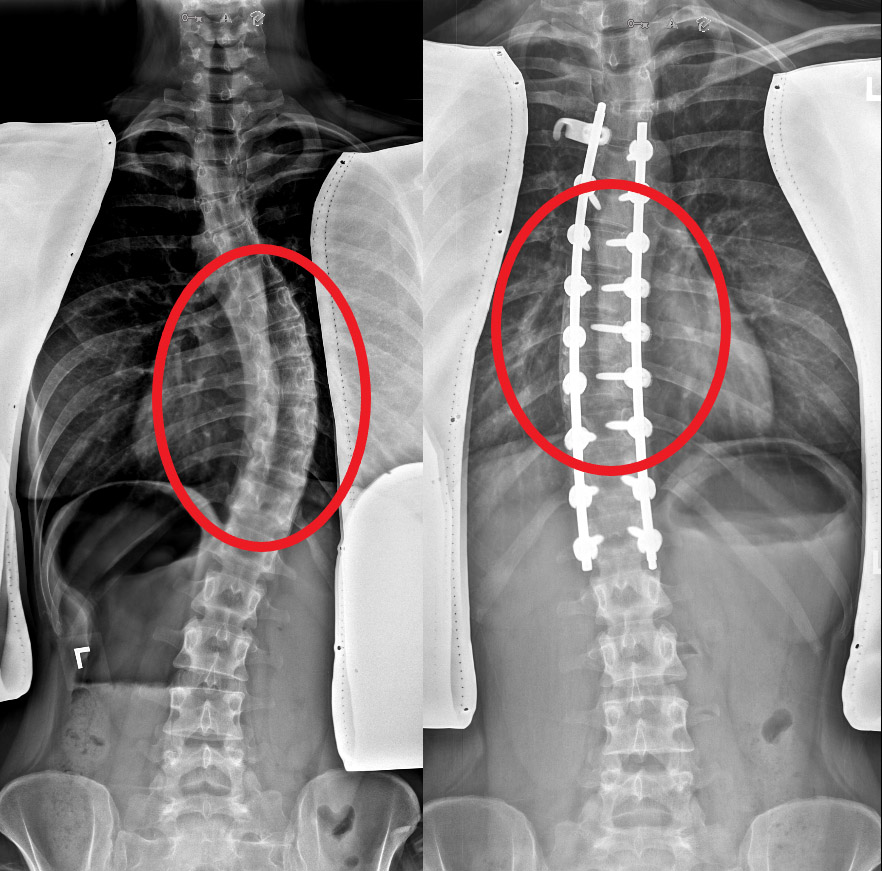

Spinal Deformity Surgery New York, NY 10019, Spinal Fusion Surgeryt Bronx Spinal Fusion Most Common Spinal Curvature Deformity The most common possible symptoms of any type of spinal deformity are: While scoliosis can occur in. Common adult spinal deformities are scoliosis, kyphosis, and lordosis. Some of the most common types of spinal deformities include: Weakness of the legs or arms. While diagnosing spinal curvature disorders, physicians typically identify four common types: This is a deformity of the lower. Most Common Spinal Curvature Deformity.

Management Strategies and Selection of Fusion Levels in Adult Spinal Deformities International Most Common Spinal Curvature Deformity Loss of sensation in the extremities. Idiopathic scoliosis is the most common spinal deformity in the world. Like other forms of scoliosis, idiopathic scoliosis affects the curvature of the spine. Lordosis is also known as swayback. Scoliosis, kyphosis, lordosis, and flatback. Scoliosis is a sideways curvature of the spine that most often is diagnosed in adolescents. The condition can create. Most Common Spinal Curvature Deformity.